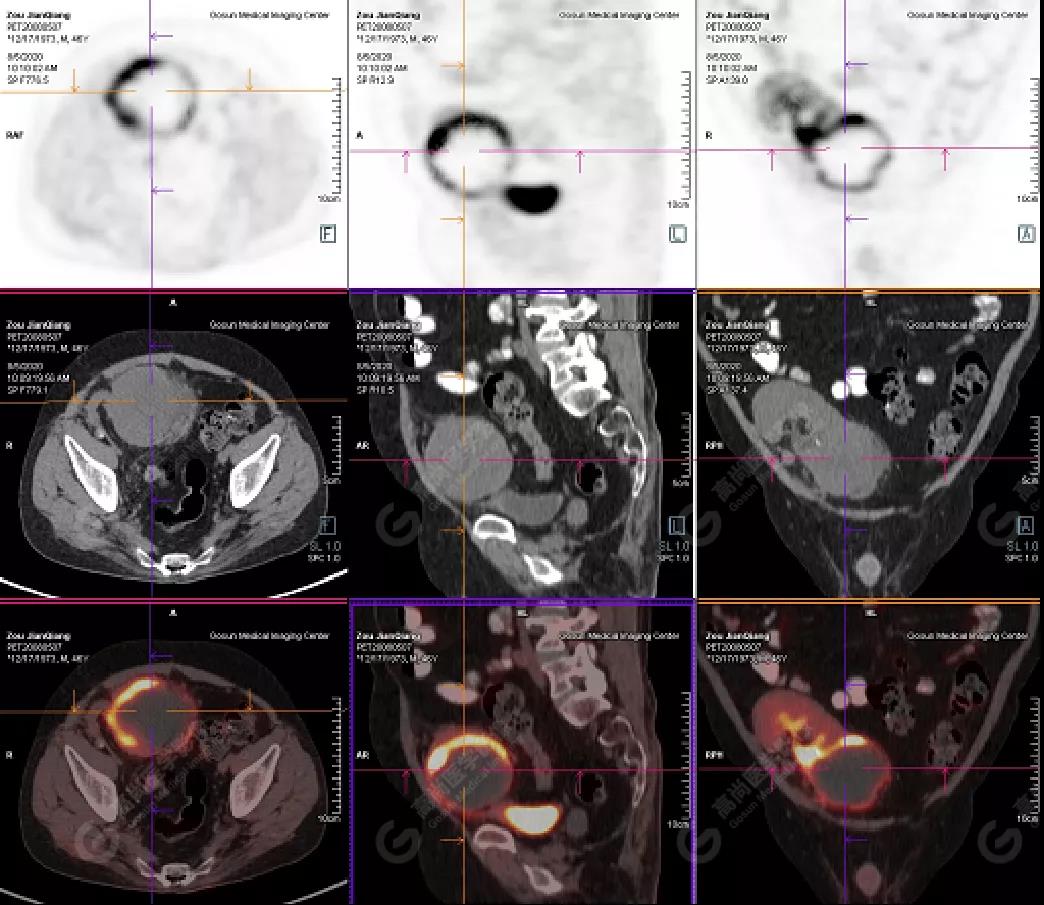

↑移植腎下部等密度腫塊,代謝環(huán)狀增高,SUVmax13.4,中心代謝缺損